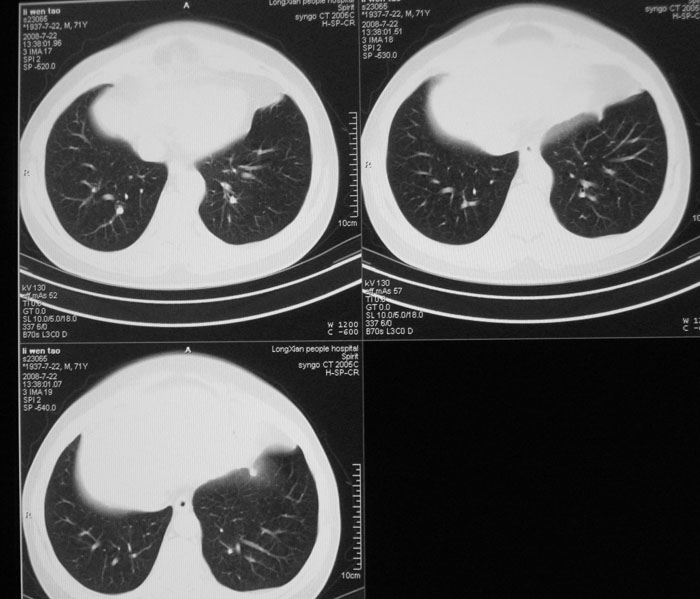

以下是引用wwwwtyy在2008-7-27 17:46:00的发言:[br]中心型肺癌不除外

以下是引用子十在2008-7-27 17:49:00的发言:[br]考虑中心性肺癌

以下是引用zhangjixiang在2008-8-6 20:02:00的发言:[br]右主支气管明显变窄伴右上叶尖段不张,结合年龄,考虑右侧中央型肺癌可能性大,纤支镜检可确诊.